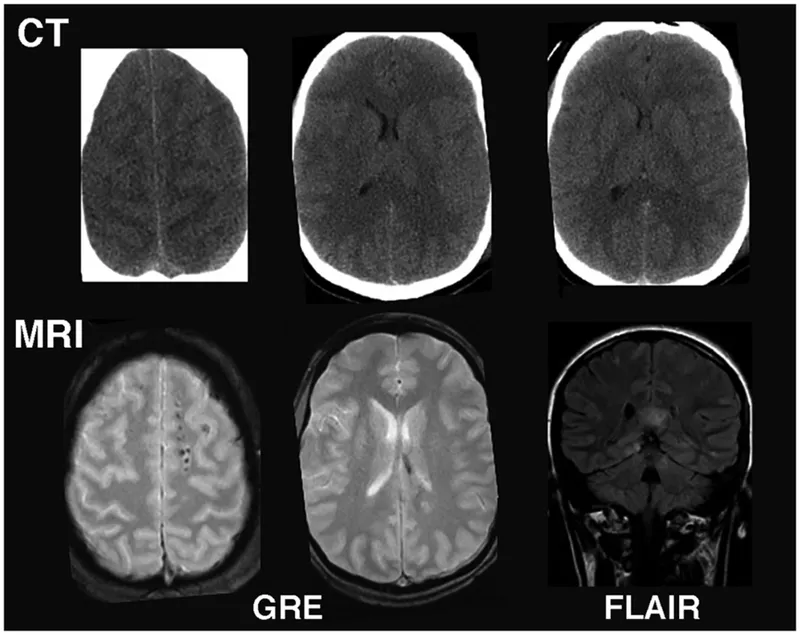

- Computed Tomography (CT)

- Principle: X-ray based; measures tissue density.

- Magnetic Resonance Imaging (MRI)

- Principle: Magnetic fields & radio waves.

- Key Sequences:

- T1-weighted: Anatomy (CSF dark). 📌 T1: Anatomy.

- T2-weighted: Pathology (CSF bright). 📌 T2: H2O bright.

- FLAIR: T2-like, CSF dark; highlights periventricular lesions (e.g., MS).